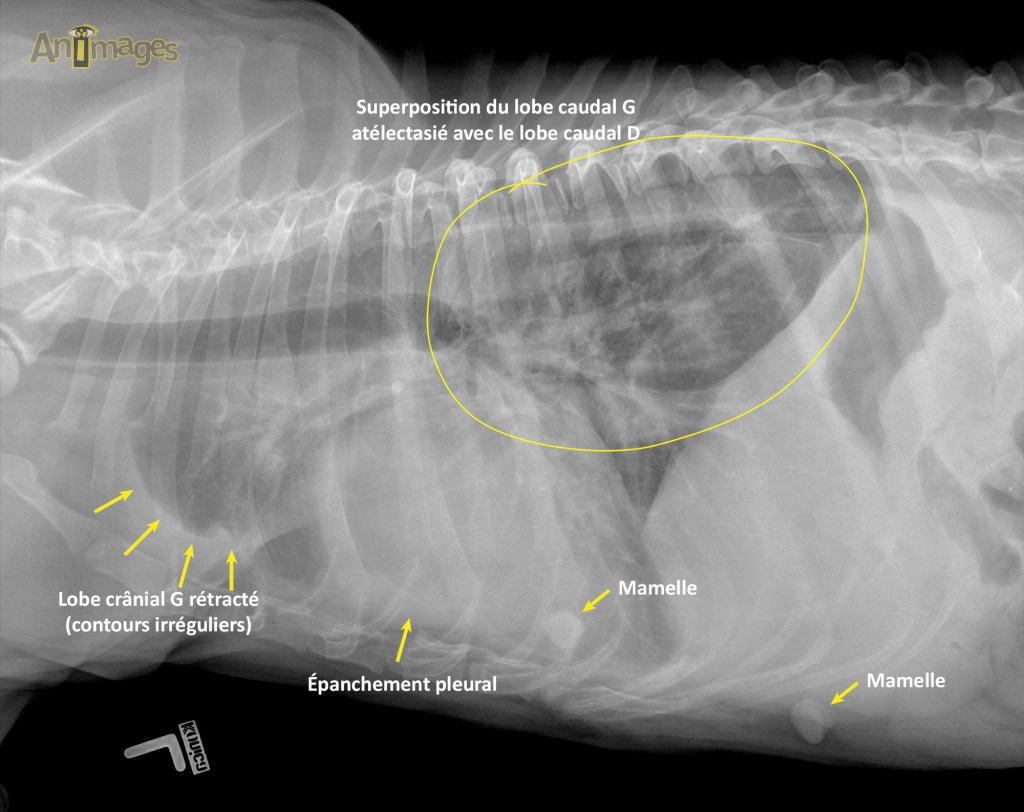

LAT G

Latérale gauche